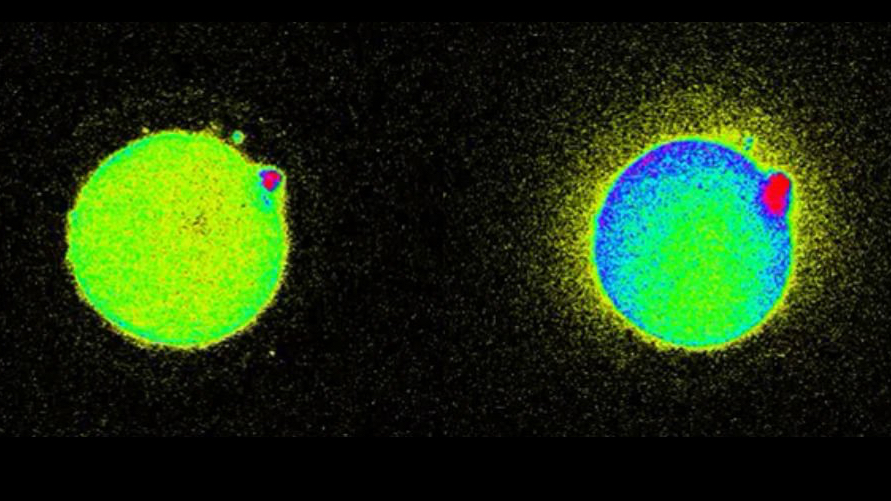

Scientists can see a spark at fertilization that has serious implications for in vitro.